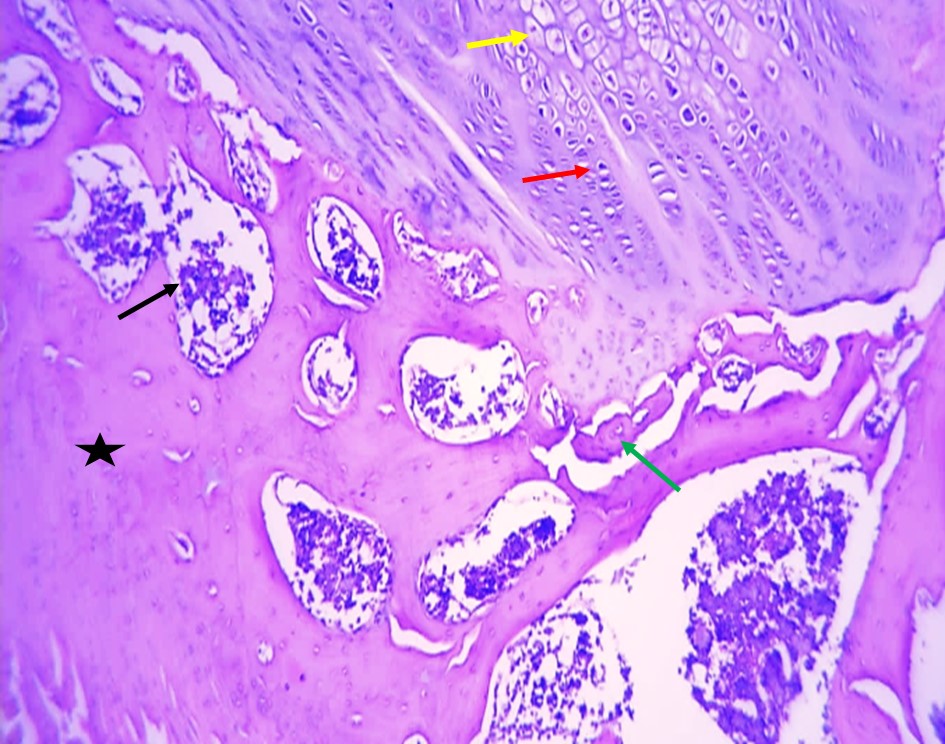

as shown Histologic al alterations in femur bone in rats with zinc deficiency in (Fig 2), involved loss of trabecular mass especially compact bone and altered osteoclast activity in the bone tissue were evaluated by atrophy in osteoblast and then decrease in bone density as compared to femur bone in rats without zinc deficiency in (Fig1) which characterized by normal architecture bone tissue showing normal compact (black star), spongy bone(black arrow) normal osteoblast (red arrow), osteoclast(yellow arrow) and normal trabecular (green arrow). Whereas the administration of zinc and Vit D cause to restoration these histological changes which including significantly improve in the trabecular mass (compact and spongy bones), improve bone density as well improve tissue remodeling and semi normal trabecular mass with normally distribution of osteoblast and osteoclast (red arrow) with good appearance of compact and spongy bone as shown in (Figs 3 and 4), the above changes in femur bone as comparison to femur bone in (Fig 2).

Figure (3).

Figure (4).

The histological alterations in femur bone its representing by loss of trabecular mass and atrophy of the osteoblast in rats femur bone with zinc deficiency inas compared to femur bone in rats without ZD which characterized by normal architecture bone tissue, this illustrates impairing bone formation by suppression osteoblast proliferation and differentiation might be attributed to elevation of oxidative stress and pro- inflammatory cytokines levels in concurrently with depletion of endogenous antioxidant status results in apoptosis of the osteoblasts, and osteocytes as well the osteogenesis and mineralization process slowdown ( 48 , 49 ). Along the same line, zinc deficiency causes dropped levels of calcium and phosphorus in bone tissue consequently impairment in bone mineralization and loss architecture ( 50 , 51 ). The obvious alleviated in the bone architecture in male rats treated within the administration of Zinc sulfate, and VitD3 which manifested by decreased the spaces, significantly improved the tissue remodeling and semi normal trabecular mass with normall distribution of osteoblast and osteoclast, this may be attributed to the zinc and Vit D possesses potential anti-inflammatory and antioxidant activities ( 52 ,). In another study by ( 54 ) who revealed that ZnHA-NPs supplementation in minimum doses have stimulatory potential impacts in the preventive and therapeutic, of osteoporosis in OVX rats. Also {55} mentioned that Zn administration with high concentration reduced pro-inflammatory mediators via suppressing the; IκB kinase (IKK)-,α/NF-κB, signaling pathway, these observations are consistent with our findings.